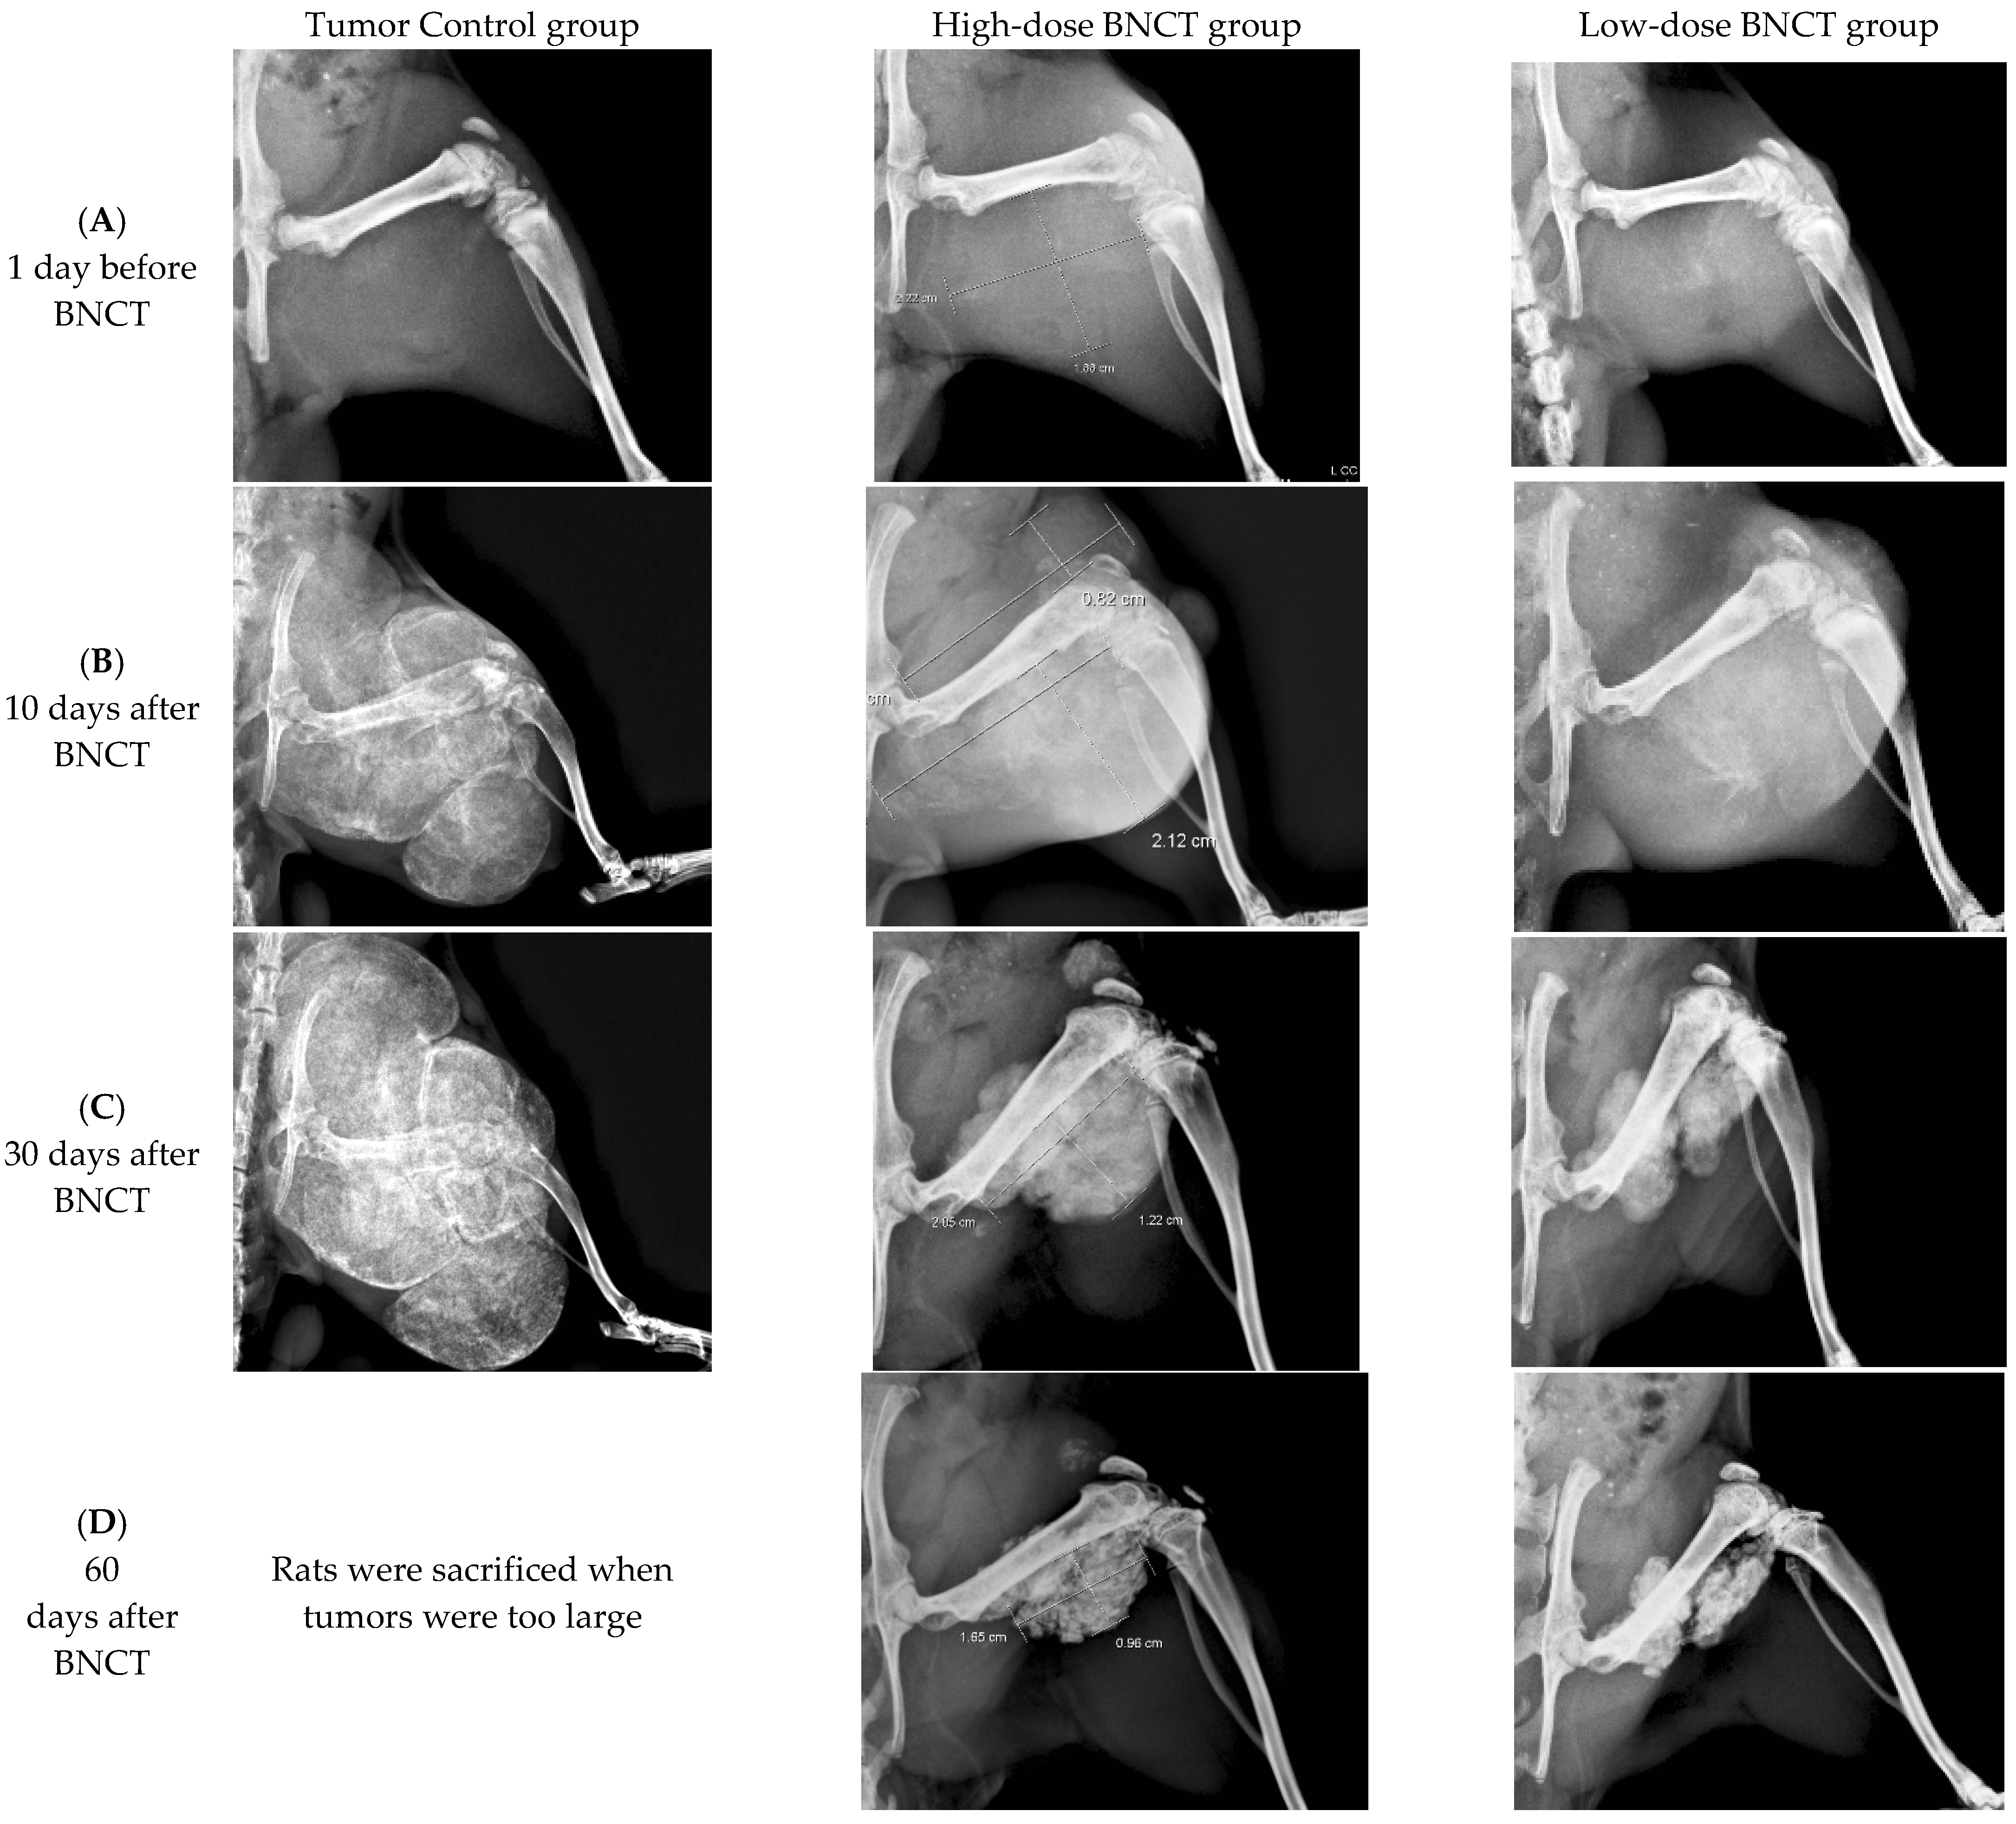

3.4.2. Radiographic Investigation